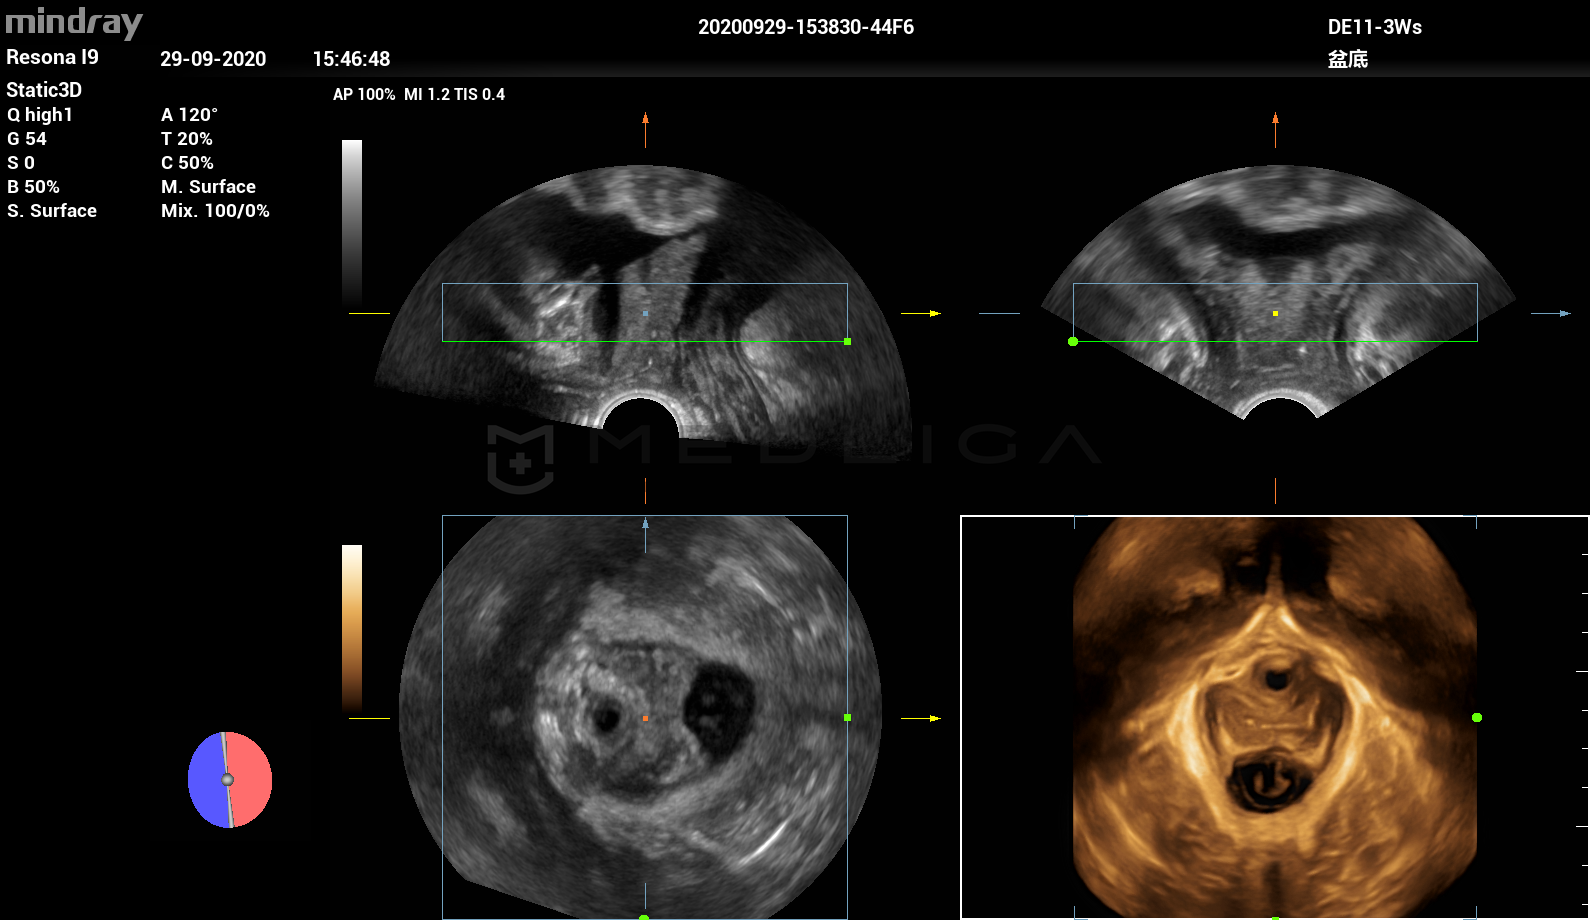

Программное обеспечение для автоматических измерений параметров и оценки функции мышц тазового дна.

Smart Pelvic - новое решение, позволяющее значительно упростить диагностическую процедуру и свести к минимуму время исследования функций мышц тазового дна. Благодаря чрезвычайно простому пользовательскому интерфейсу, программа генерирует стандартную систему координат и автоматически просчитывает все связанные измерения в течение нескольких секунд.